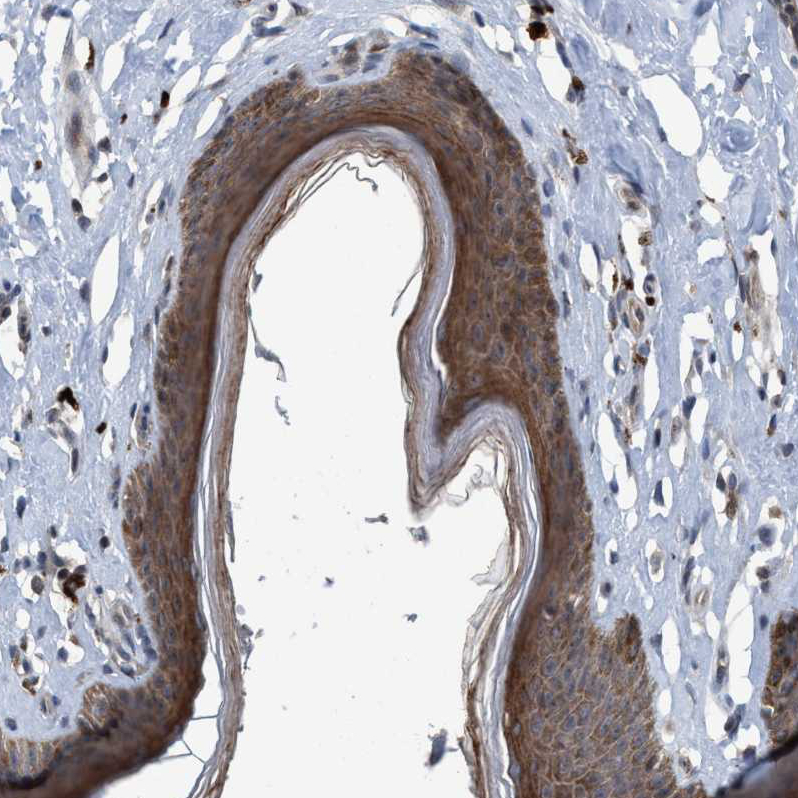

Immunohistochemical staining of human cerebellum shows strong cytoplasmic and membranous positivity in Purkinje cells.